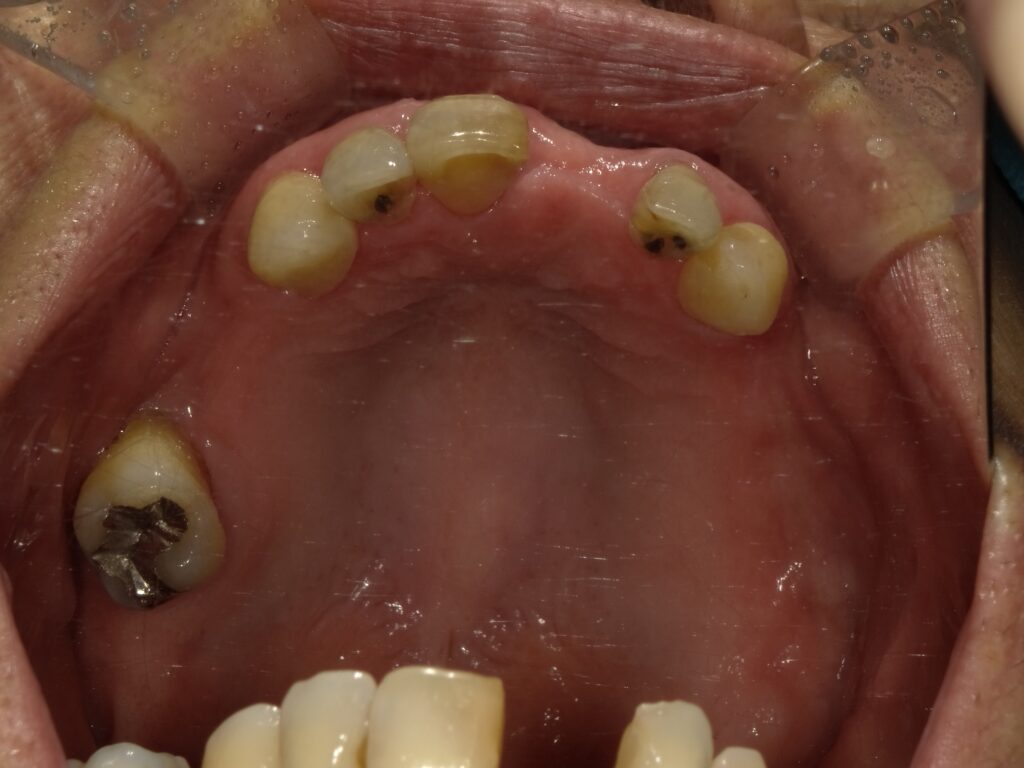

BEFORE

AFTER

主訴

全体的に見た目を綺麗にしたい。奥歯でしっかり噛みたい。

診断名・主な症状

臼歯部欠損

年齢

65歳

治療内容

インプラント埋入(左下5・6,右下5・6,左上4・6)

サイナスリフト(左上4・6)

ジルコニアBr(右上6−左上3)

E –MAX CAD(右下4)

セラミックインレー(左下4)

治療期間/

通院回数

約1.5年/約20回

費用

インプラント治療 約2,000,000円

その他被せ物治療など 約1,000,000円

合計 約3,000,000円

*いずれも税込